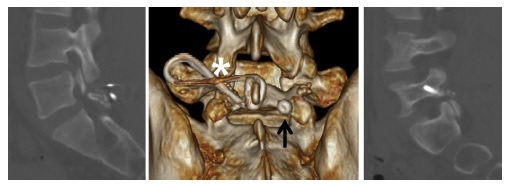

研究的观察指标包括:VAS 疼痛评分、ODI 功能评分和 SF-12 健康量表评分。其中 SF-12 健康量表评分包括物理评分和精神评分两个部分。影像学上的观察指标包括:峡部裂缺口间距和融合率。峡部不愈合定义为 CT 上融合骨块不连续(图 2 和图 3)。

图 2 术后 1 年的 CT 提示峡部愈合(右侧,星号)和不愈合(左侧,箭头)